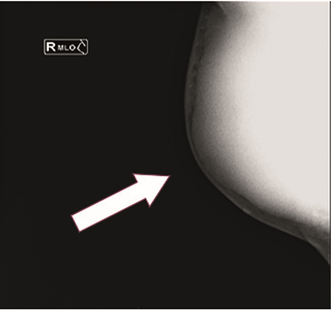

Male, 65 years old, originally from a rural community, farmer, incomplete primary school, married, Catholic. His mother had gastric cancer, the patient reported heavy smoking for 40 years, at a rate of ten to fifteen cigarettes per day, social alcoholism at a rate of two beers per month. Her condition began in April 2018 with pain in the right mammary gland, presence of a palpable, painful mass, with an increase in pau Latin volume, movable, with a stony sensation, sudden weight loss in six months, approximately 15 kg, intolerance to the oral route, unchanged excretions. In November 2018, she underwent an evaluation by a surgical oncologist, who indicated that she should undergo paraclinical and laboratory studies, with results of a BI-RADS 5 breast ultrasound and BI-RADS 5 mastography suggestive of malignancy (Figures 1 & 2).

Figure 2 Mammography with mediolateral-oblique projection and evidence tumor in the region of the right mammary gland.